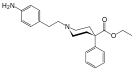

The first fully synthetic opioid was meperidine (later demerol), found serendipitously by German chemist Otto Eisleb (or Eislib) at IG Farben in 1932.[228] Meperidine was the first opiate to have a structure unrelated to morphine, but with opiate-like properties.[199] Its analgesic effects were discovered by Otto Schaumann in 1939.[228] Gustav Ehrhart and Max Bockmühl, also at IG Farben, built on the work of Eisleb and Schaumann. They developed "Hoechst 10820" (later methadone) around 1937.[230] In 1959 the Belgian physician Paul Janssen developed fentanyl, a synthetic drug with 30 to 50 times the potency of heroin.[211][231] Nearly 150 synthetic opioids are now known.[228]